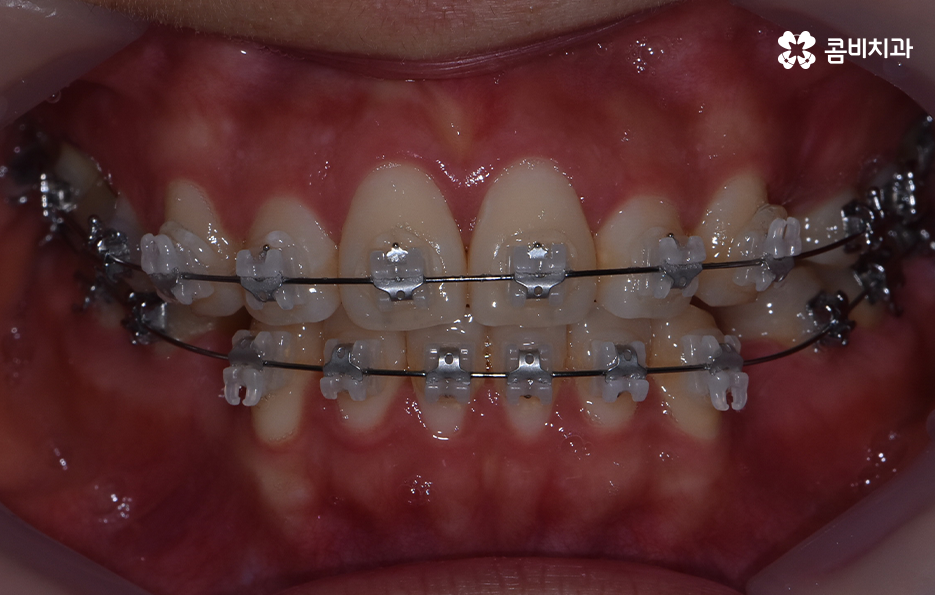

오늘은 돌출입발치교정 통해서 치열도 가지런하게 교정하고 얼굴형의 변화뿐 아니라 교합까지 잘 맞물려서 건강하게 치아교정을 하는 방법에 대해 알아볼 거예요

이처럼 치열의 변화는 얼굴형 변화에도 많은 영향을 줄 수 있기 때문에 치아교정의 만족도는 치열뿐 아니라 환자 개개인의 골격과 얼굴형을 고려하여 잘 어울리는 조화적인 측면과 치아의 건강 등 고려해야 할 점이 많다는 것을 알 수 있는데요

치아교정을 잘하기 위해서는 자신의 구강 구조 및 얼굴형 등을 종합적으로 정밀 검진하여 경험 많은 교정 전문의와 충분한 상담의 필요하며 수많은 돌출입발치교정 사례가 존재하기에 나에게 맞는 치료 방법을 잘 아는 것이 중요하다는 것을 강조드리고 있어요